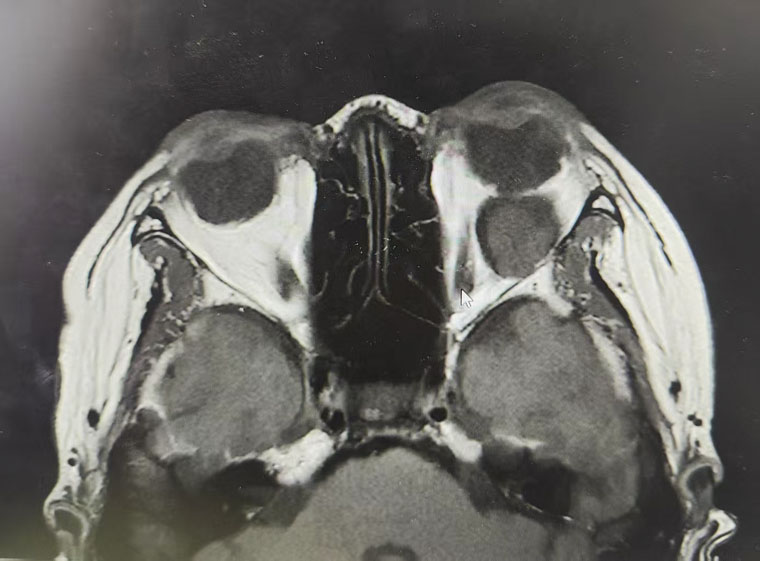

该患者因“发现右眼眼球逐渐突出2年”就诊于我院,眼眶CT检查显示,眼球正后方隐藏着一个与眼球等大的肿物,占位效应明显。眼球后方空间狭小、结构精密,如何在这一关键区域将体积较大的肿瘤完整剥离,同时保护视神经、眼外肌等重要解剖结构不受损伤,加之患者明确要求面部不能留下疤痕,这些因素均对手术精准度与微创性提出了极致挑战。

术前

术后